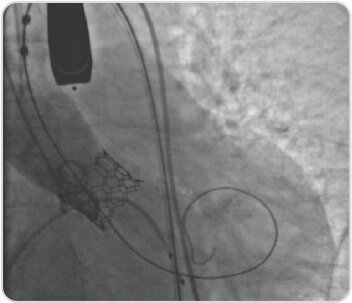

Trans Catheter Aortic Valve Implantation (TAVI) – Case-1

80 years old lady presented with effort intolerance of 6 months duration. Evaluated and found to have severe calcific aortic stenosis and normal coronaries. TAVI done successfully with 21.5 mm balloon expandable Myval (Meril, India).